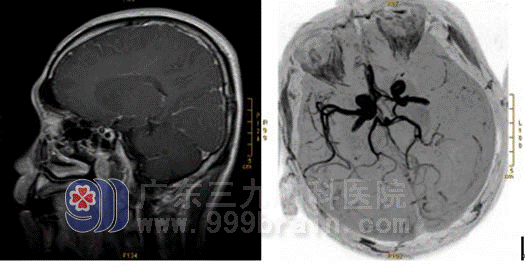

Magnetic resonance showed:

Blood supply section of left brain had lots of infarction, two sides of thalamencephalon had infarction, MRA showed his left brain had artery emphraxis.